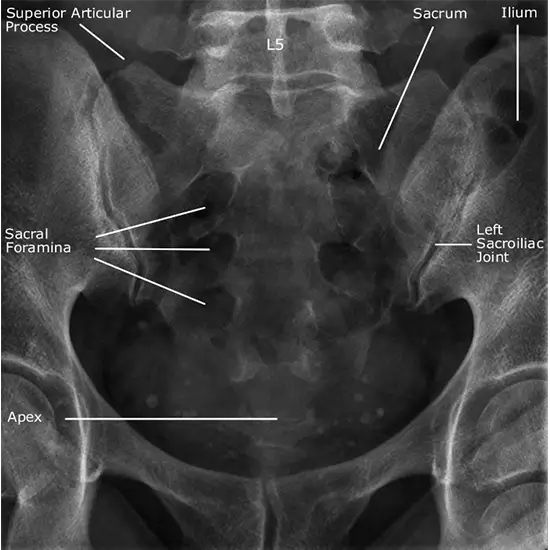

X-Ray Sacral AP/Lateral

The X-Ray Sacral AP & Lateral View radiography can help in the diagnosis of the certain sacral conditions and traumatic injuries. By taking an accurate frontal (AP) and lateral (Lateral) image of the sacrum, the X-Ray Sacral AP & Lateral View can help in diagnosing degenerative conditions, injuries, and dislocations. This helps in diagnosing trauma-related conditions, postoperative recovery, chronic pain. At Medifyhome, you can be assured of accurate results since we use the latest x-ray equipment and professional radiologists. To get a full assessment and timely care, plan your scan right away.

What is an X-Ray Sacral AP/Lateral View?

The X-Ray Sacral AP & Lateral View is a diagnostic non-invasive radiography procedure utilized to view the structure and alignment of the sacral bones. For sacral fractures, arthritis, and postural abnormalities, doctors use the AP (Anterior-Posterior) View and the Lateral View to diagnose the problem. This imaging is often suggested to patients with low back pain, PTSD, and post-operative evaluations.